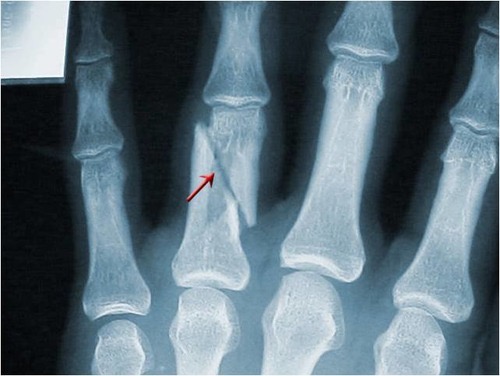

Avulsion fracture

A fracture in which a fragment of bone has been pulled away by a tendon and its attachment. Common in children